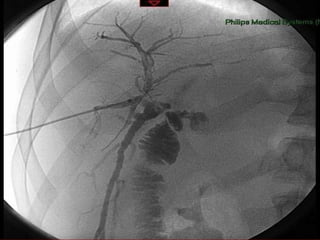

RECOMENDAÇÕES Colangiograma intraoperatório Técnica Não evita, mas diagnostica SABER INTERPRETAR US intraop como alternativa Strasberg, JACS, 1995; 180: 101 Massarweh, Surgery, 2008; 207:821 Flum, JAMA 2003; 289: 1639 Flum, JACS 2003: 196:385

RECOMENDAÇÕES Colangiograma

RECOMENDAÇÕES Colangiograma intraoperatórioTécnica Não evita, mas diagnostica SABER INTERPRETAR US intraop como alternativa Strasberg, JACS, 1995; 180: 101 Massarweh, Surgery, 2008; 207:821 Flum, JAMA 2003; 289: 1639 Flum, JACS 2003: 196:385